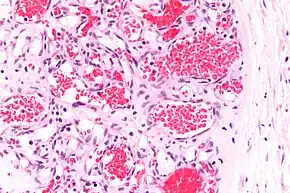

Capillary hemangioma

Strawberry naevus, H&E stain

A precise history of the growth characteristics of the IH can be very helpful in making the diagnosis. In the first 4 to 8 weeks of life, IHs grow rapidly with primarily volumetric rather than radial growth. This is usually followed by a period of slower growth that can last 6–9 months, with 80% of the growth completed by 3 months. Finally, IHs involute over a period of years.[34] The exceptions to these growth characteristics include minimally proliferative His, which do not substantially proliferate[33] and large, deep IHs in which noticeable growth starts later and lasts longer.[34] If the diagnosis is not clear based on physical examination and growth history (most often in deep hemangiomas with little cutaneous involvement), then either imaging or histopathology can help confirm the diagnosis.[31][35] On Doppler ultrasound, an IH in the proliferative phase appears as a high-flow, soft-tissue mass usually without direct arteriovenous shunting. On MRI, IHs show a well-circumscribed lesion with intermediate and increased signal intensity on T1- and T2-weighted sequences, respectively, and strong enhancement after gadolinium injections, with fast-flow vessels.[31] Tissue for diagnosis can be obtained via fine-needle aspiration, skin biopsy, or excisional biopsy.[36] Under the microscope, IHs are unencapsulated aggregates of closely packed, thin-walled capillaries, usually with endothelial lining. Blood-filled vessels are separated by scant connective tissue. Their lumina may be thrombosed and organized. Hemosiderin pigment deposition due to vessel rupture may be observed.[37] The GLUT-1 histochemical marker can be helpful in distinguishing IHs from other items on the differential diagnosis, such as vascular malformations.[32]